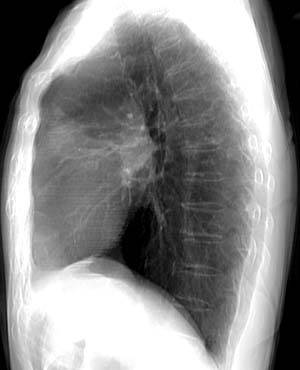

Re-projection image from volumetric data

Data acquired by R. Kato M.D., processed by K. Katada M.D.

Copyright (c) 1999 by Fujita Health University. All rights reserved.